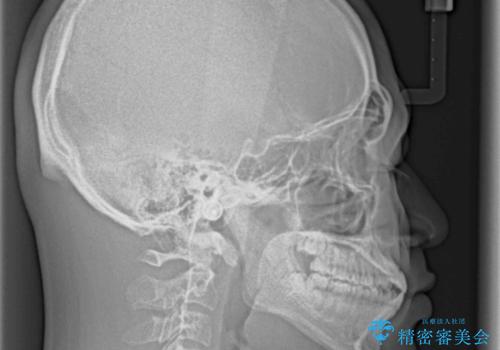

空隙歯列を閉じる 舌のトレーニングとワイヤー矯正

- 上下前歯の隙間を気にして来院された患者様です。

飲み込みや話をするときに舌を突出させる癖が強くあり、それが原因でスペースが空いていました。

舌癖を改善するためのトレーニングを行いながら、ワイヤー装置を用いて前歯の隙間を閉じていくこととしました。

舌の突出癖がなかなか改善されず、治療期間は当初予定よりも大分長くなりました。

装置除去を予定していた日に、油断されたのか1mmほどのスペースを作ってしまったため、除去が3ヶ月延長されたことで、舌のトレーニングの重要性を理解していただきました。

装置除去後もトレーニングを継続されているようで、後戻りによるスペースは今のところ認められておりません。